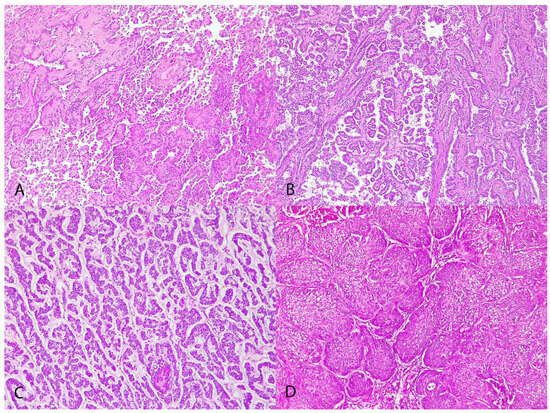

Histologically, tumors were classified as lepidic (2/19, 10.52%) (Figure 1A), papillary (13/19, 68.42%) (Figure 1B), micropapillary (1/19, 5.26%) (Figure 1C), and squamous (3/19, 15.78%) (Figure 1D). Tumors were grade I in 7 cases (36.8%), grade II in 10 (52.6%), and grade III in 2 cases (10.5%).

Figure 1. Canine pulmonary adenocarcinomas. (A) Lepidic pattern; H&E; objective 10×; dog n 15. (B) Papillary pattern; H&E; objective 10×; dog n 19. (C) Micropapillary pattern; H&E; objective 10×; dog n 12. (D) Squamous pattern; H&E; objective 10×; dog n 17.